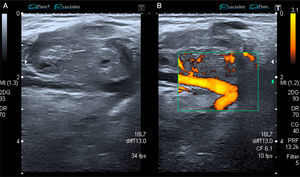

The patient was a 53-year-old man with no significant medical history. He presented with a painless mass in anterior forearm, reporting no previous injury. Physical examination confirmed the presence of a hard, immobile mass measuring less than 1cm. He came to the rheumatologic examination room, where he underwent soft tissue ultrasound (Toshiba Aplio®300). A round mass measuring less than 1cm was observed. It was iso/hypoechoic on gray scale images, was moderately well-defined, and was joined to a vessel that fed it (Fig. 1). On color Doppler, there was high echo intensity throughout the entire lesion, more intense on the periphery (Figs. 2 and 3). As there were findings that raised suspicion, such as heterogeneity, the marked vascularity and the marked Doppler signal (grade 3), magnetic resonance imaging was performed. This study revealed a round, well-defined form measuring 1cm, with hyperintensity on T1-weighted images, which pointed to a metastatic lesion (Fig. 4).

This case is useful in clinical practice in rheumatology because: (1) the images can raise suspicion for the seriousness of a nodular lesion smaller than 1cm because of its vascularity and heterogeneity; (2) it highlights the importance of the rheumatologic examination room in the diagnosis of soft tissue tumors (benign or malignant) that rheumatologists should not disregard; (3) cutaneous metastases of prostatic adenocarcinoma are very uncommon and, in this case, soft tissue ultrasound helped to orientate the extensive study of the neoplastic disease; and (4) it is essential to identify the lesions on the basis of their ultrasonographic appearance and, when in doubt, the study should be extended to include magnetic resonance imaging.4